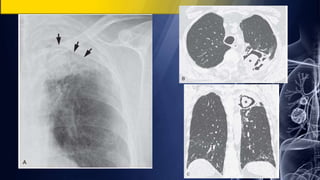

67-year-old man with hemoptysis and prior tuberculosis

• PA chest radiograph demonstrates a cavitary left apical mass with an intrinsic

soft tissue nodule and an air-fluid level. Air crescent sign

• unenhanced chest CT (lung window) demonstrates a left apical thick-walled

cavitary lesion with an intrinsic dependent soft-tissue nodule and small cavitary

satellite nodules. An adjacent pleural thickening as well as left apical

centrilobular and paraseptal emphysema.

Aspergillosis; Mycetoma

67-year-old man withhemoptysis and prior tuberculosis • PA chest radiograph demonstrates a cavitary left apical mass with an intrinsic soft tissue nodule and an air-fluid level. Air crescent sign • unenhanced chest CT (lung window) demonstrates a left apical thick-walled cavitary lesion with an intrinsic dependent soft-tissue nodule and small cavitary satellite nodules. An adjacent pleural thickening as well as left apical centrilobular and paraseptal emphysema. Aspergillosis; Mycetoma